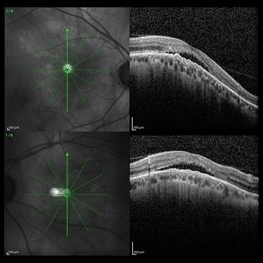

Foveal Detachment in Dome-Shaped Macula

May 6 2017 by Mitzy E Torres Soriano, MD

Vertical scans of optical coherence tomography showing a foveal detachment at the top of dome-shaped macula in a 48-year-old female with high myopia.

Photographer: Mitzy E. Torres Soriano

Condition/keywords: detachment, high myopia, macula